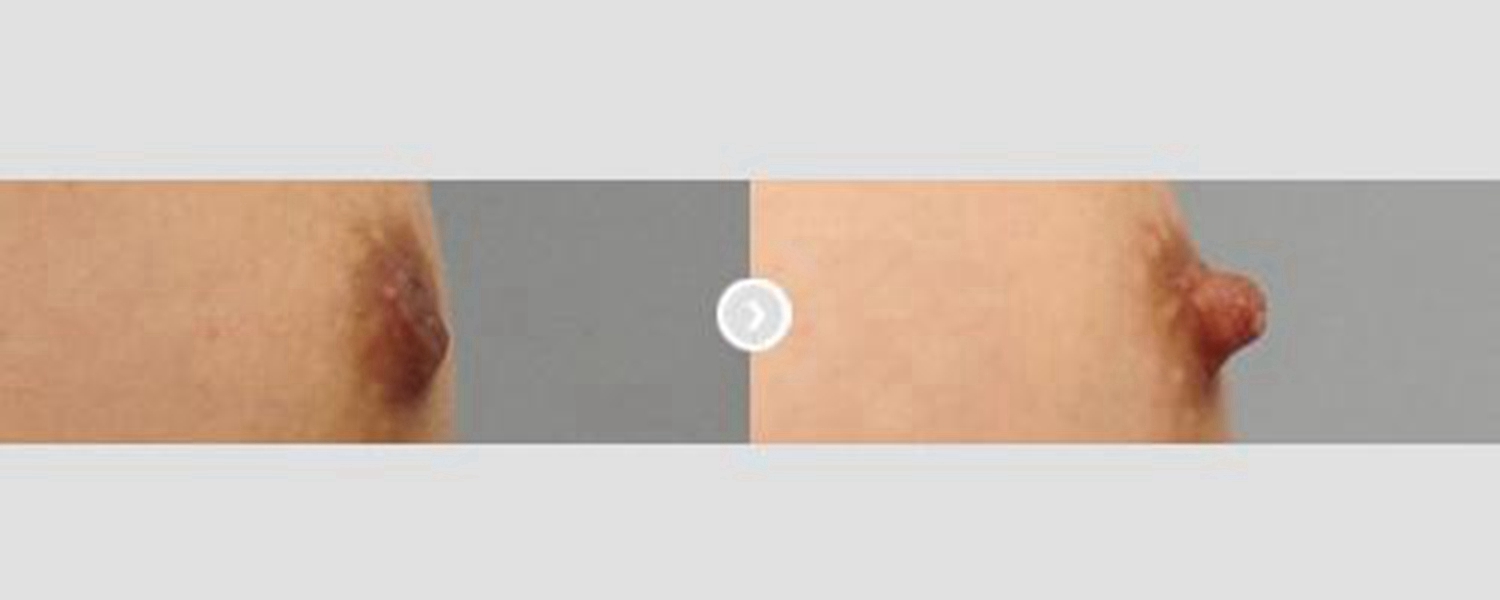

乳頭內陷治療效果

中度乳頭內陷矯正